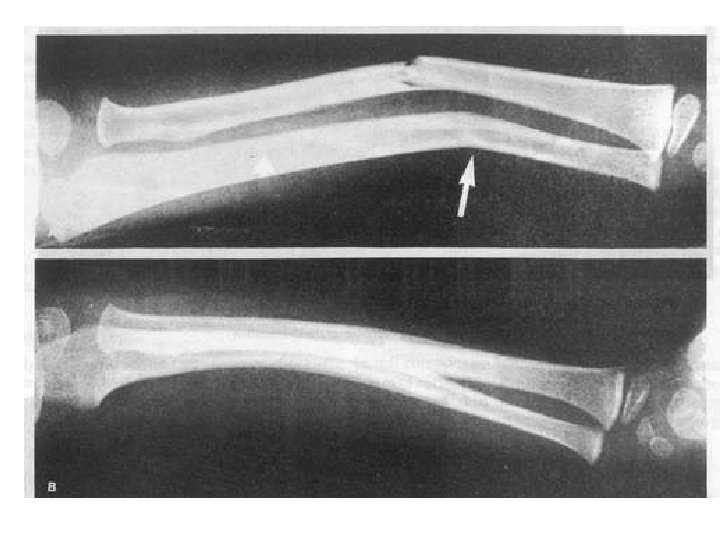

Fracture paterns Hair line Fr Transvers Fr Depress Fr Oblique Fr Spiral Fr Green

Fracture paterns Hair line Fr Transvers Fr Depress Fr Oblique Fr Spiral Fr Green stick Fr Cominuted Fr Compres Fr Segmental Fr Epiphyseal Fr Impacted Fr